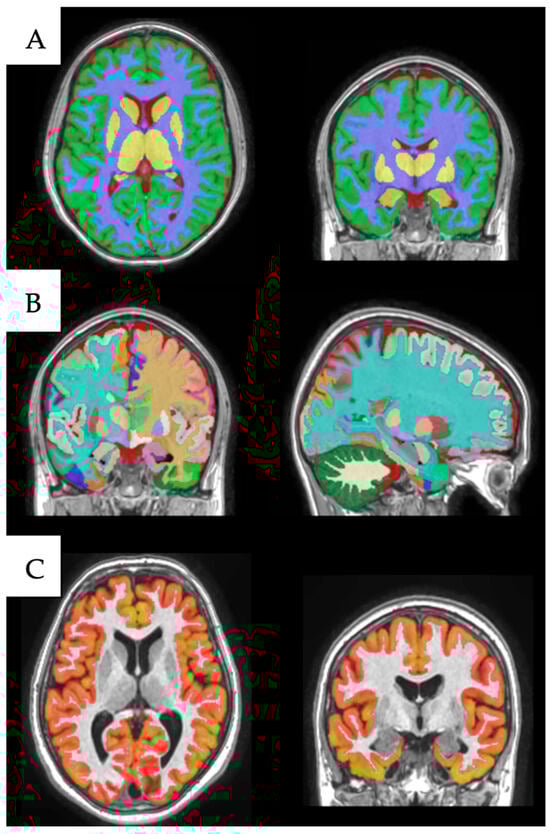

2.3. Image Processing

Volumetric Analysis with volBrain